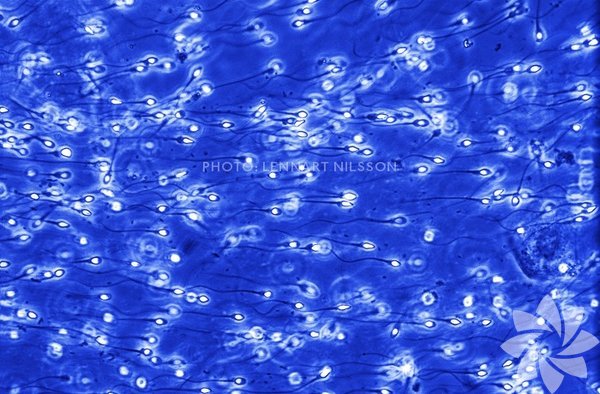

Fotoğrafçı Lennart Nilsson, özel yöntemler kullanarak spermin yumurtayla buluşmasından doğuma kadar, bir bebeğin oluşmasının ilginç aşamalarını görüntüledi.

Vajina kanalında rahim ağzına doğru ilerleyen spermler.

İçlerinden sadece biri (ya da ikiz-üçüz olacaksa, birkaçı) yumurta hücresine ulaşabilecek.